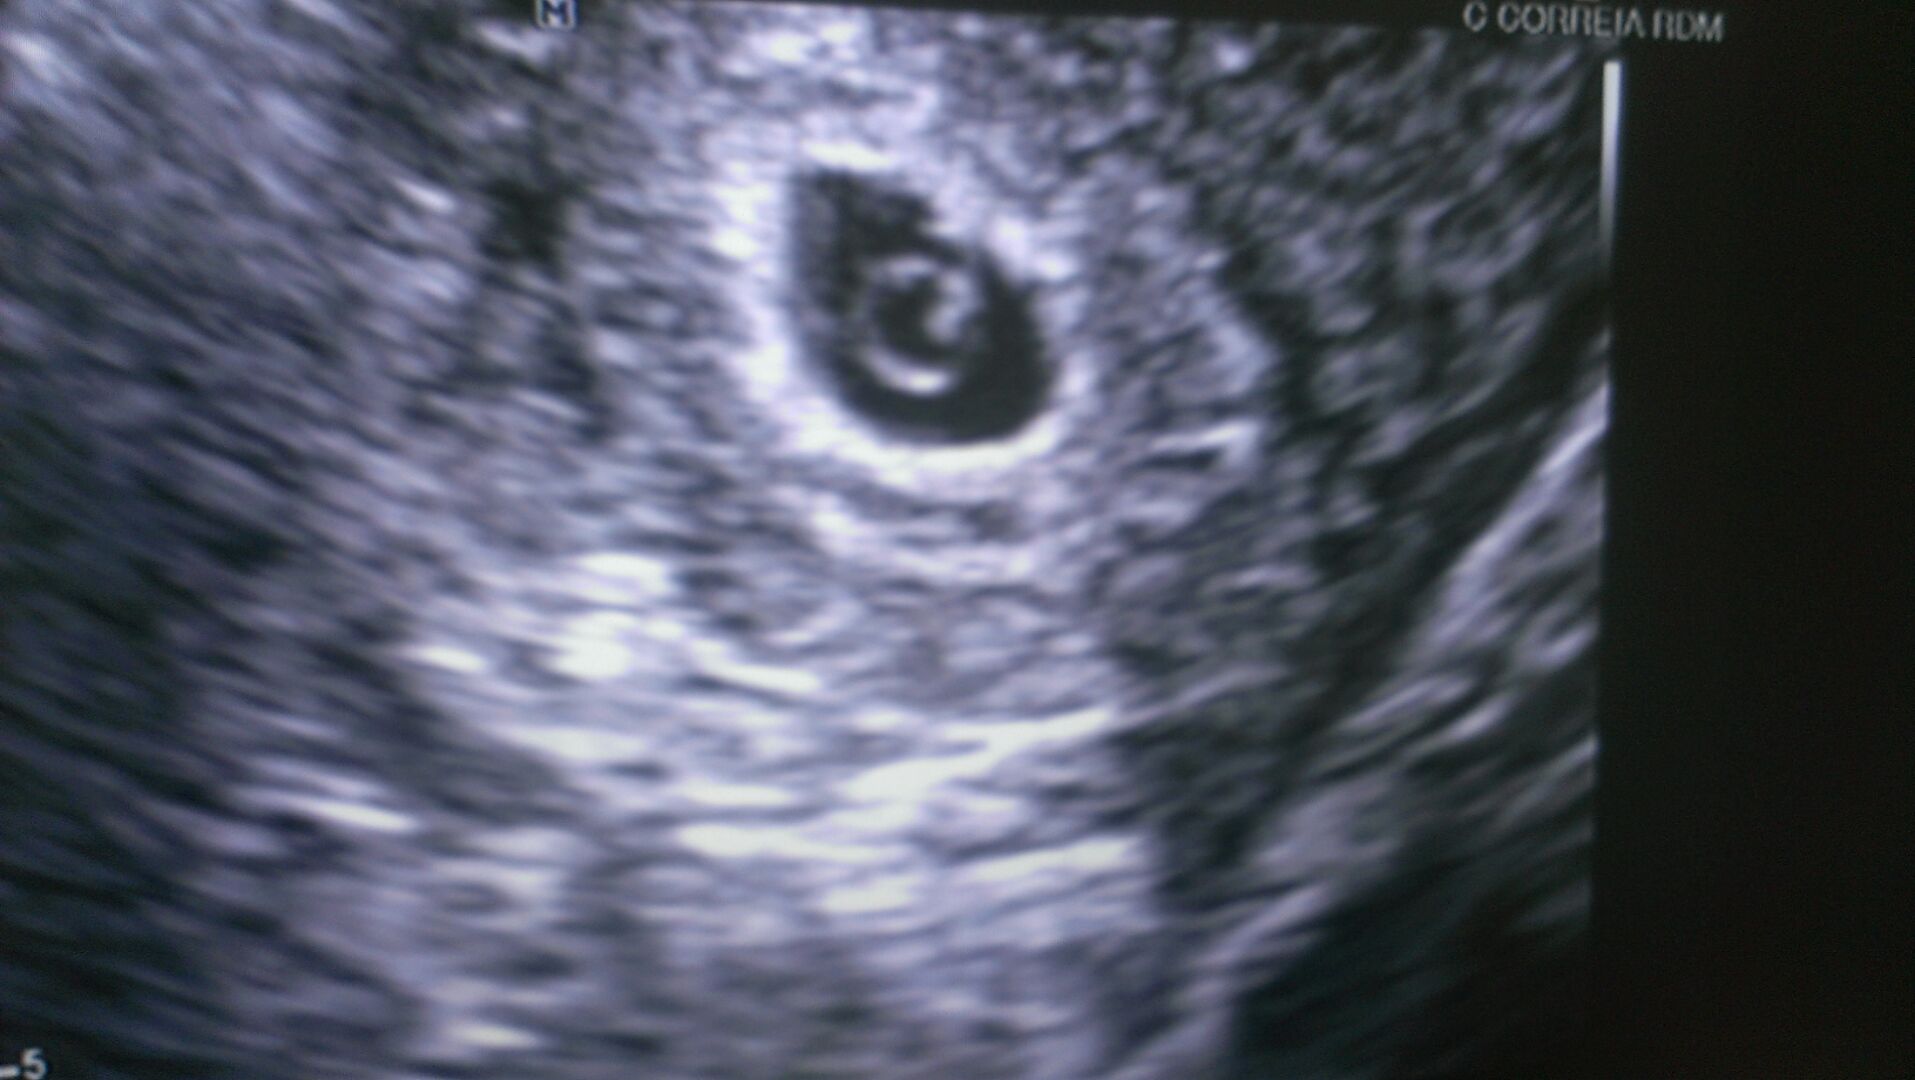

Woke up this morning with a tiny amount of brown spotting. Since I've miscarried before, I decided to call my dr and they were able to squeeze me in for an ultrasound early this AM. Low and behold a baby measuring exactly 6 weeks, 6 days which is where it should be. They saw a heartbeat too! I'm so overjoyed, and am celebrating that I am pregnant TODAY and trying to not think too much about the future. Bleeding has since stopped. She said could have been from intercourse or heavy lifting. Here's our bean: